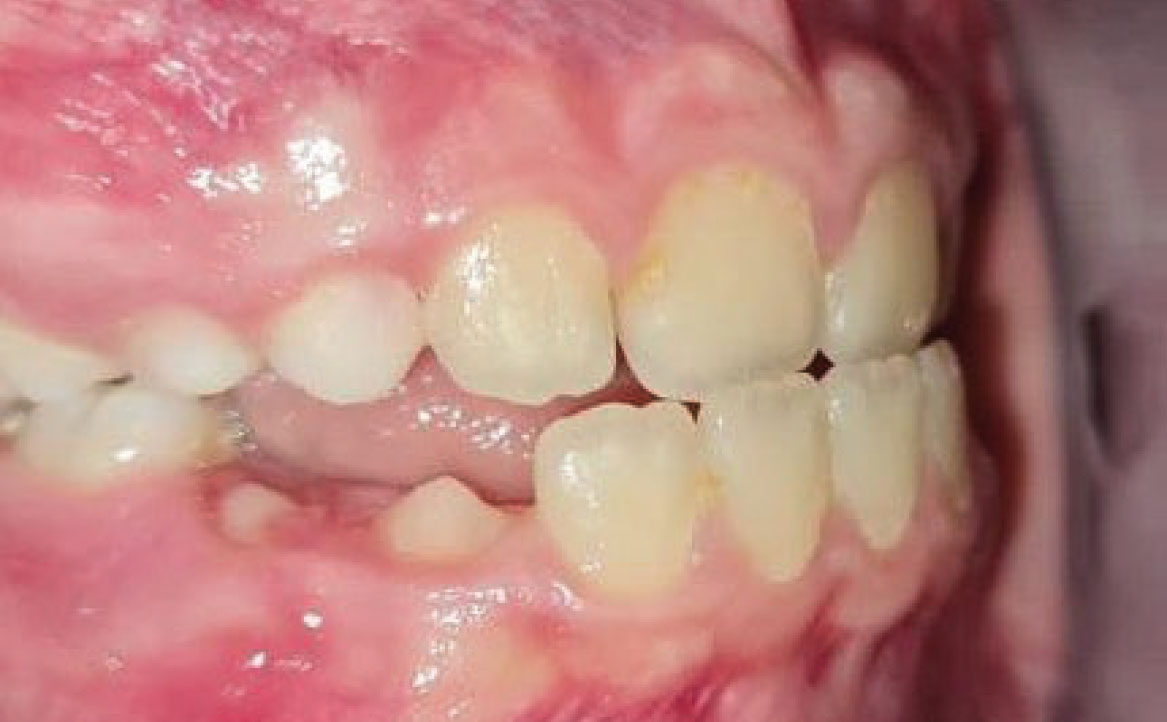

Fig. 4C Foto intraorale in massima intercuspidazione.

A livello intraorale sul piano sagittale è osservabile I classe molare destra e sinistra e classe canina non valutabile per mancanza degli elementi dentari durante la fase di permuta.

L’overjet e l’overbite sono entrambi ridotti in massima intercuspidazione. Trasversalmente il mascellare superiore è contratto (fig. 4-7).